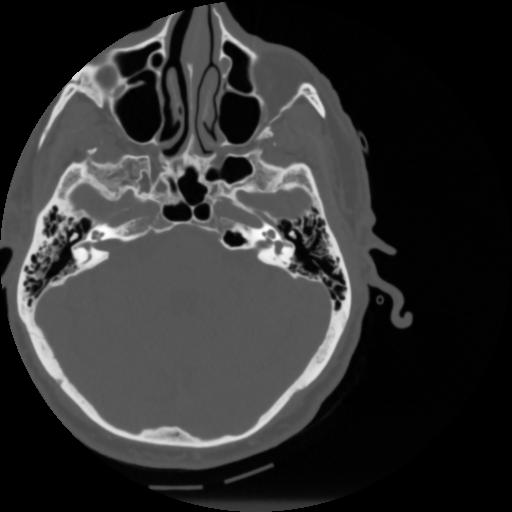

4 CEREBRO,,Vol,0.5,CEREBRO,,